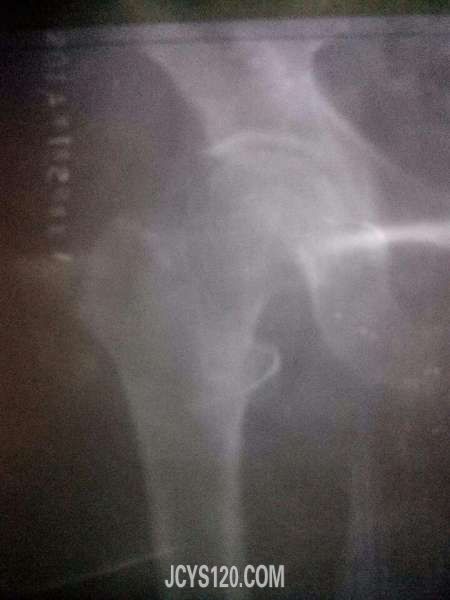

患者,王xx 女 62岁,因被电动撞倒在地,车子砸到左侧髋关节处,感觉疼痛,但可而难受,随来我院拍x光片,请各位前辈帮忙分析,左侧骶髂关节是否有骨折。 阅读全文>

病人自诉有关节疼痛,关节内注射曲安奈德注射液和B12针后仍有疼痛,前俩天去中医院拍的片子,大家看看啊! 阅读全文>